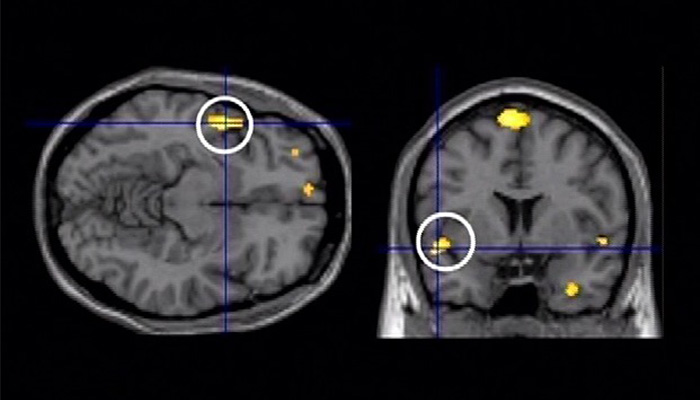

The following six episodes of the program showcase the latest discoveries regarding various human senses, including sight, smell, touch and taste.

1. Optical Illusions Reveal the Mysteries of Sight / 錯覚から迫る視覚の謎

6. The Science behind the Sixth Sense / 科学が迫る“第六感”